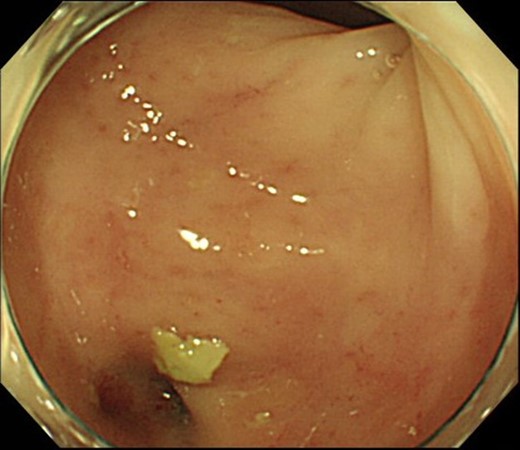

Case 2 was a 58-year-old man with a BMI of 30.3 kg/m2. Robot-assisted LAR and ileostomy was performed for lower rectal cancer over the past 2017 years, and a 1/2 circumferential fistula around the 6 o’clock direction was recognized on postoperative colonoscopy (Fig. 4). The patient was diagnosed as having a grade A anastomotic leakage without symptom because of the anastomotic leakage. He was discharged on POD 26 and was followed up on an outpatient basis. Contrast imaging performed simultaneously with endoscopic examination 6 months after the operation showed remarkable improvement of the abscess cavity, but it still remained (Fig. 5a and b). The anastomotic leakage improved 11 months after surgery (Fig. 6), but a polyp was found on the anal side 2 cm from the anastomotic site and was resected. Adenocarcinoma, pTX, ly0, v0, pHMX, and pVMX were diagnosed. The tumor was followed up because the depth of penetration, the deep stump, and the horizontal stump remained unknown (Fig. 7). Regarding the polypectomy site, no abnormality was found in the examination 8 months after resection of the polyp. Therefore, ileostomy closure was performed 18 months after the first operation (Fig. 8). Postoperatively, it took some time to improve the intestinal movement with paralytic ileus, but the patient was discharged 18 days after surgery. The Wexner score one month after closure was 18 points and still showed high anal dysfunction but the patient was under observation at the outpatient department.

Colonoscopy shows a true lumen (circle) and an abscess cavity (arrow) with drainage of pus.